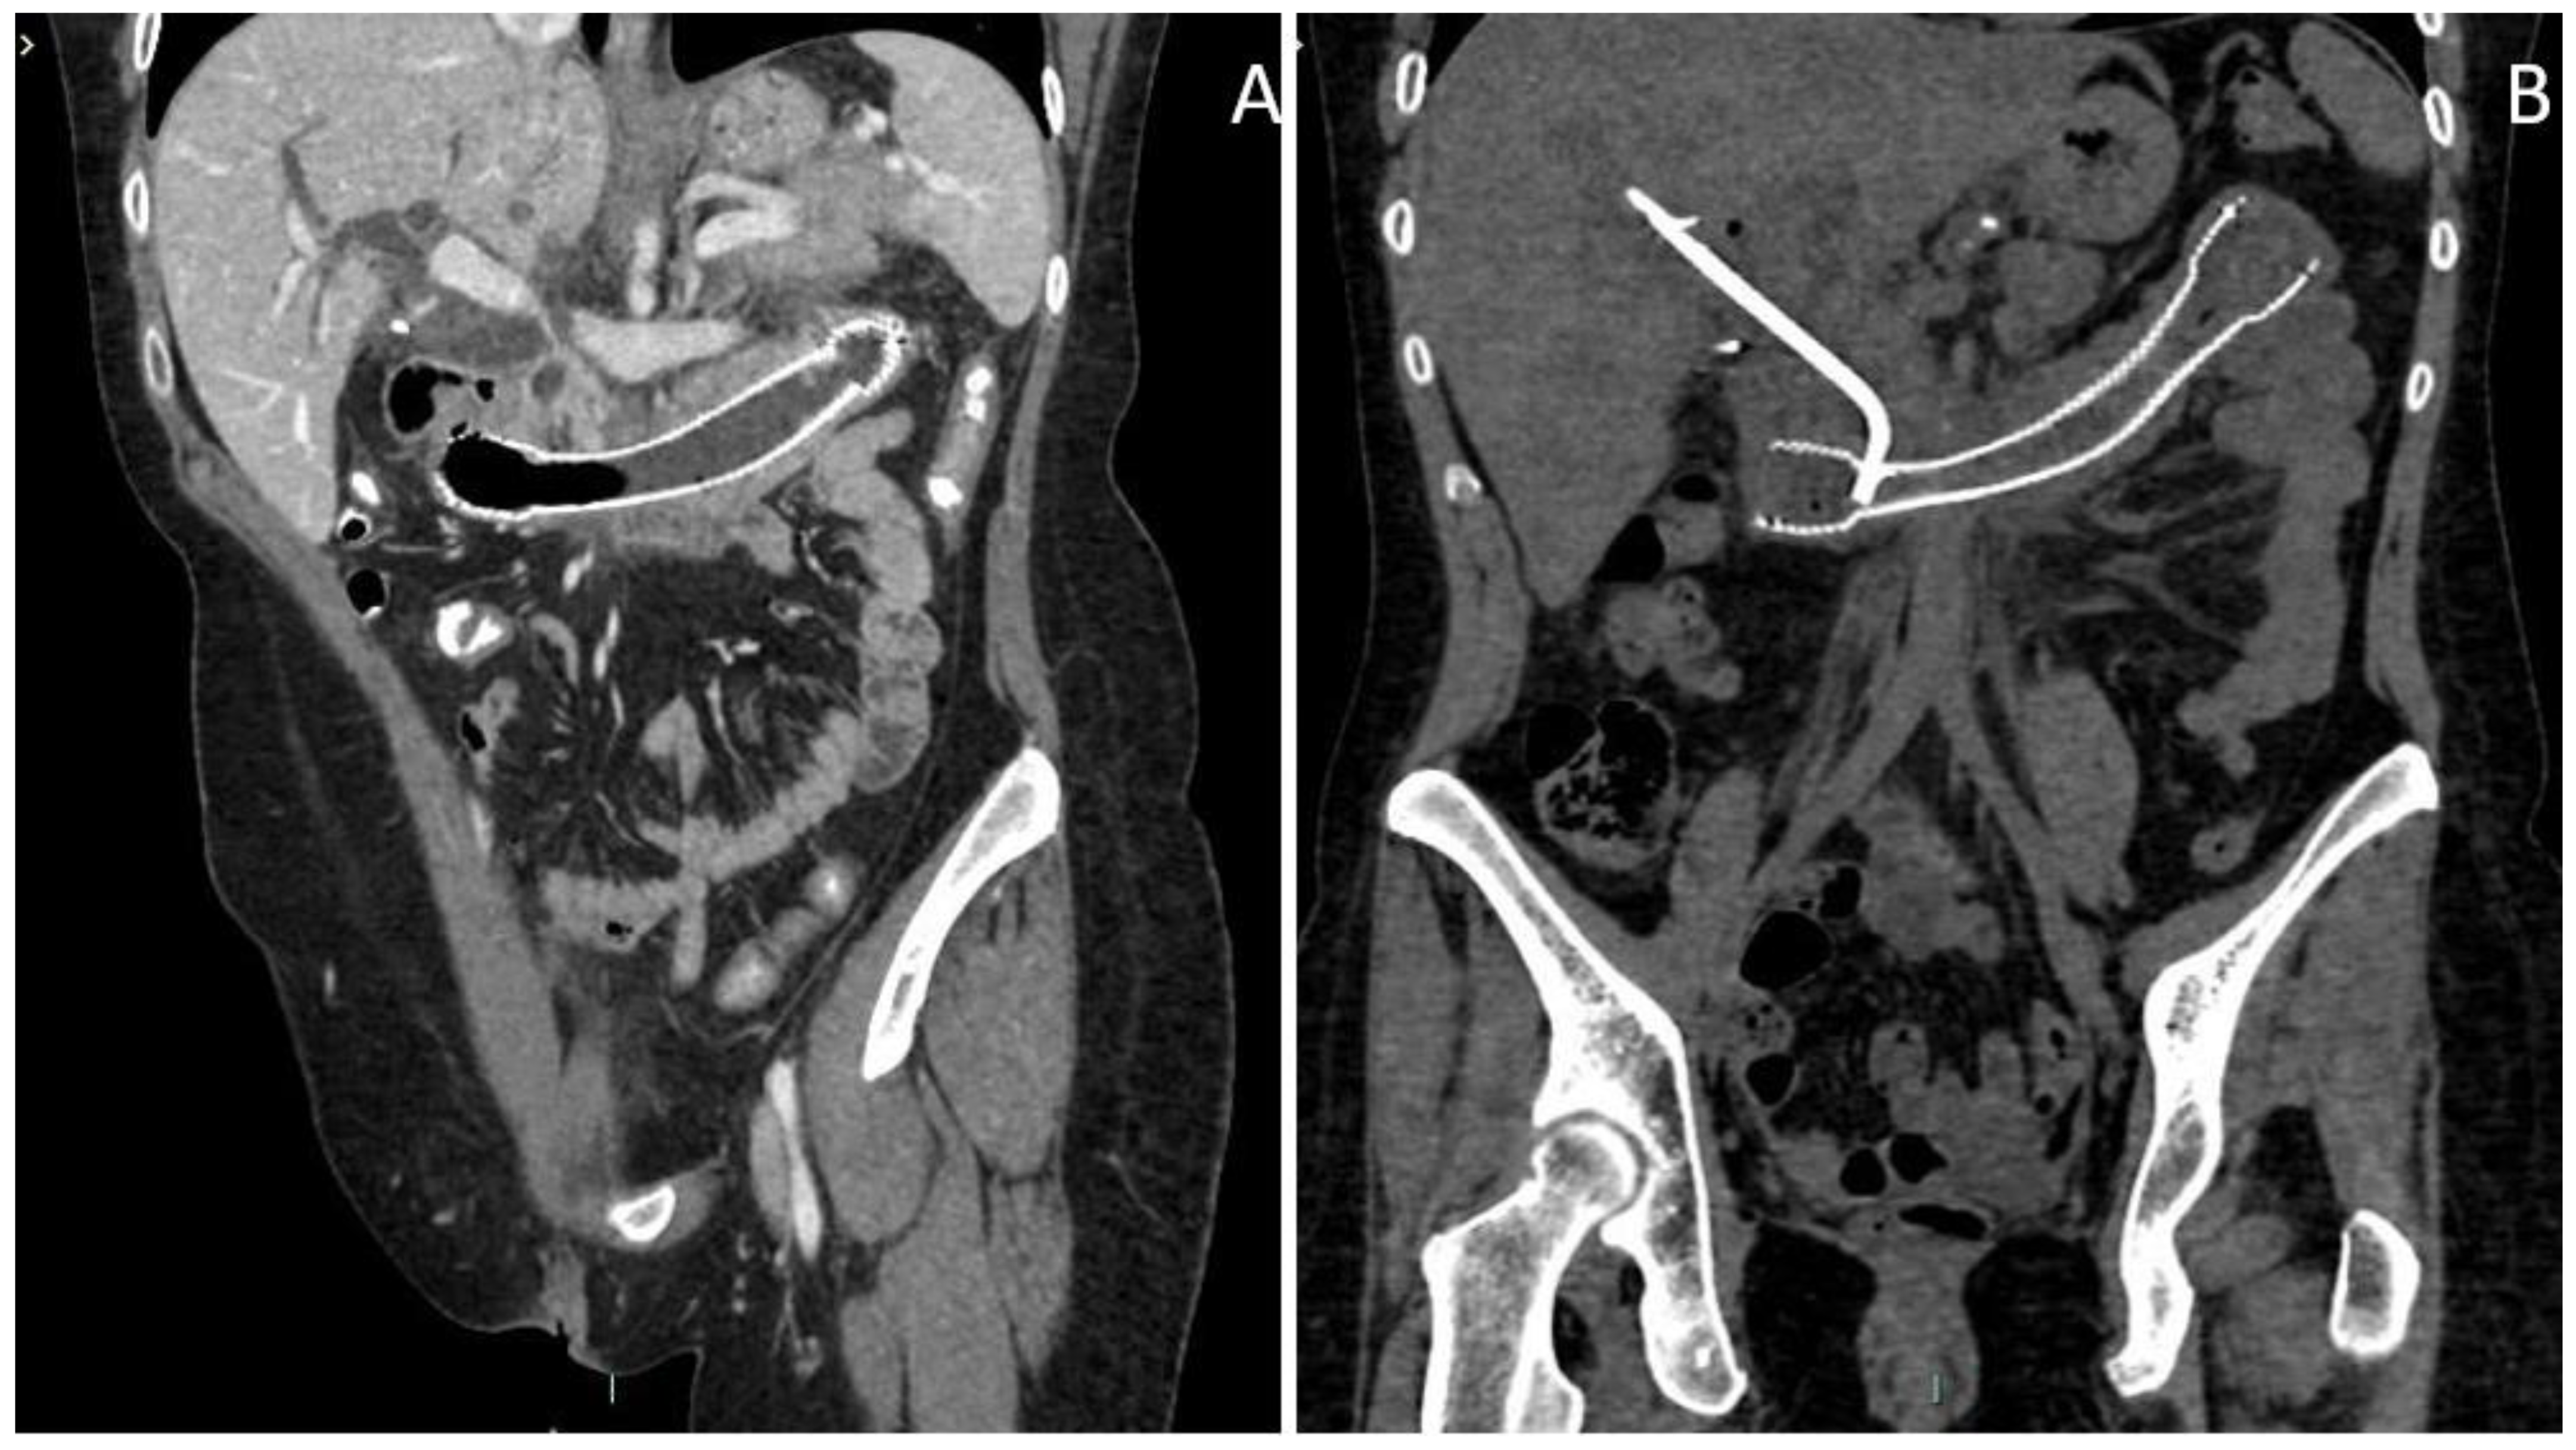

2. Case Discussion